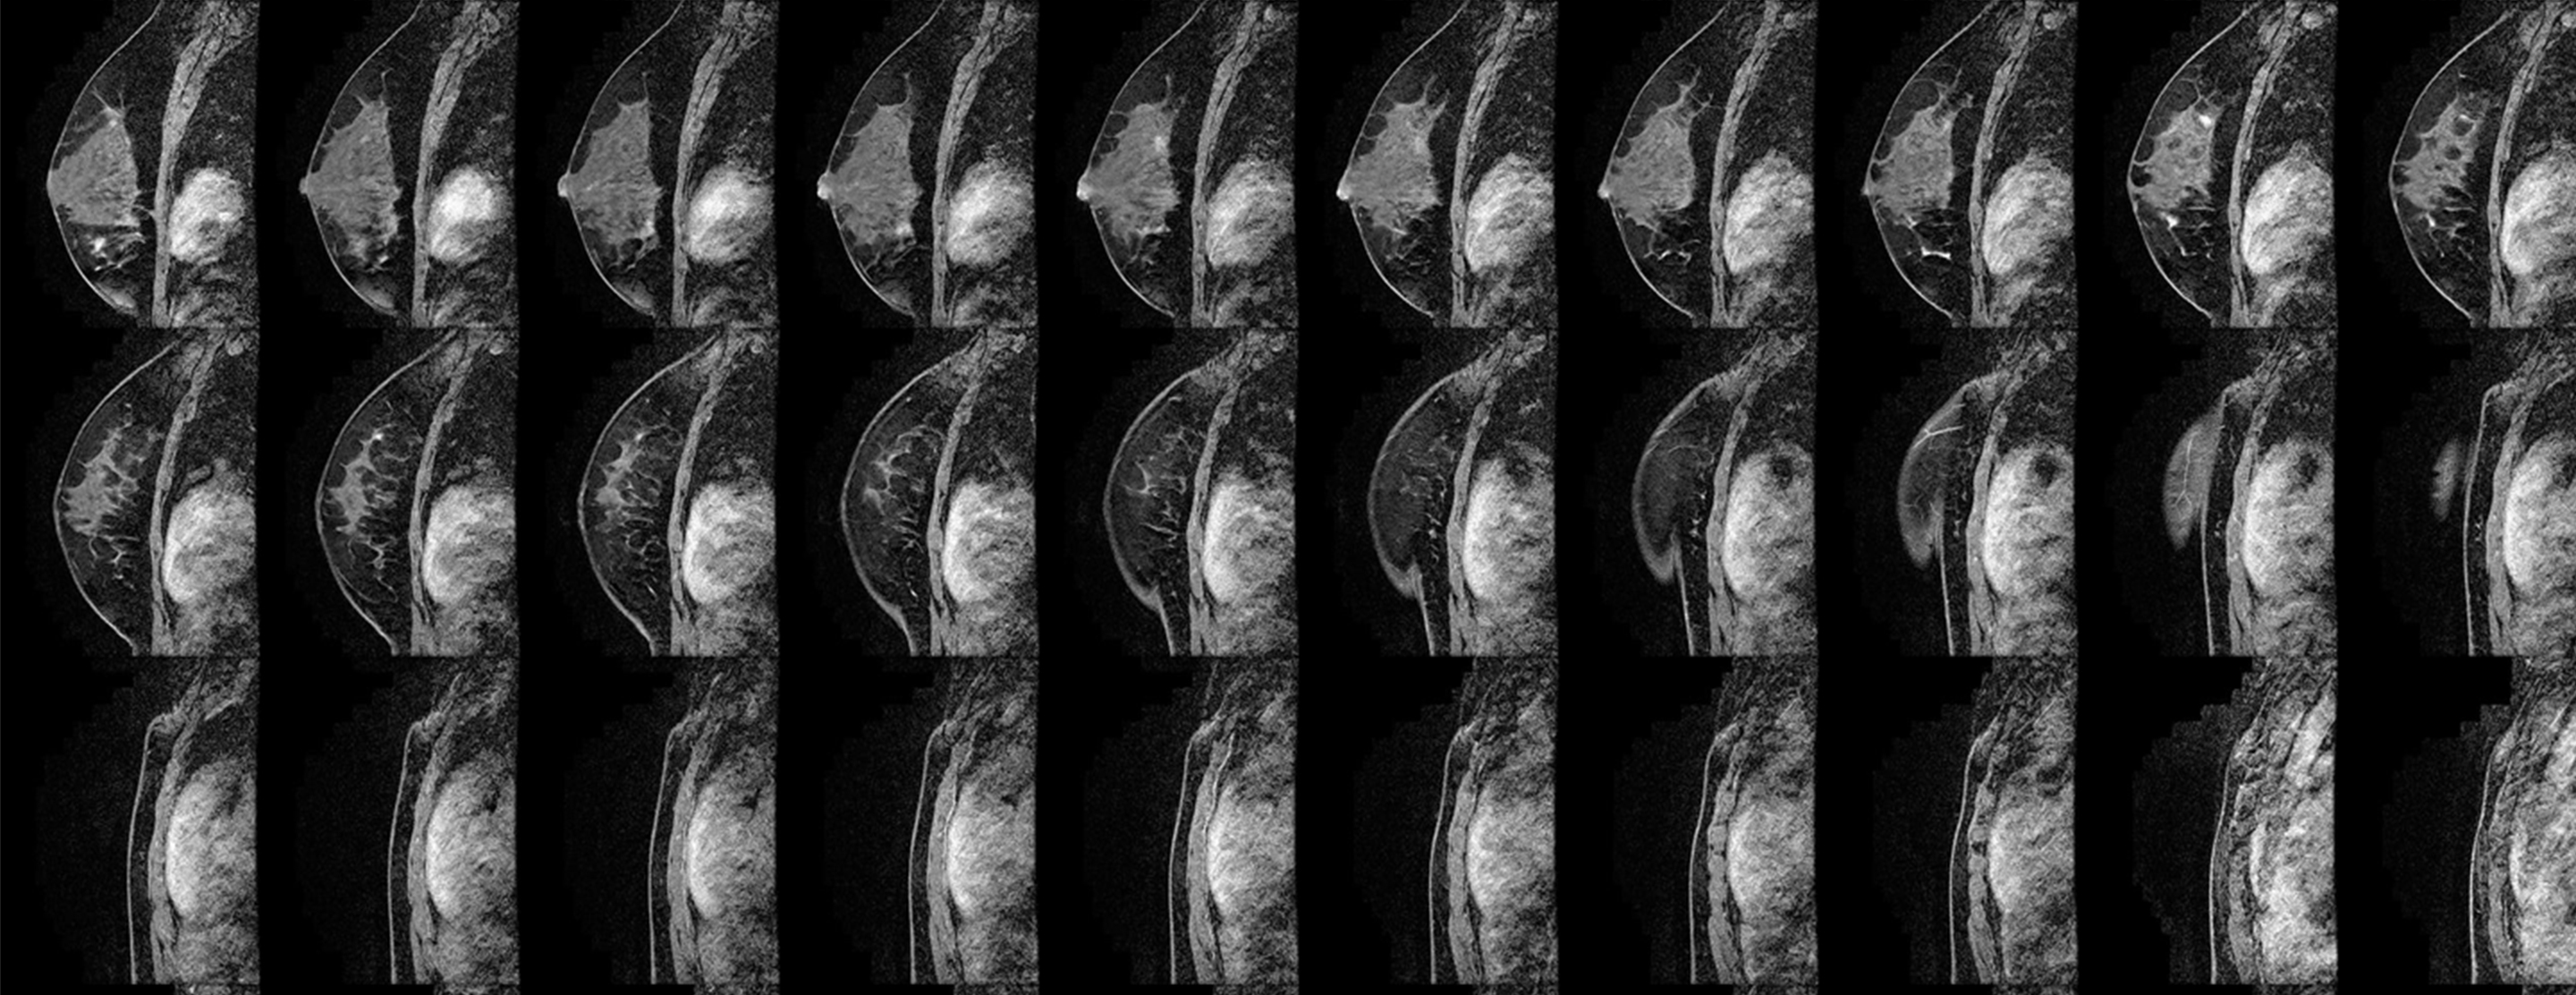

If an MRI detects an abnormality in your breast that can't be seen on a mammogram or with ultrasound, your doctor may recommend an MRI-guided core biopsy. This is less invasive than a surgical biopsy and causes little to no scarring. During the procedure, the doctor uses MRI to locate the abnormal tissue and take a small sample for evaluation.

You stay awake during the procedure, lying facedown on a padded MRI scanner table that has a cushioned opening for your breast. The opening is surrounded by a device called a breast coil that holds the breast in place and works with the machine to create images. The MRI technologist takes images for five to 10 minutes to precisely locate the abnormality. You need to remain very still during this part of the procedure.